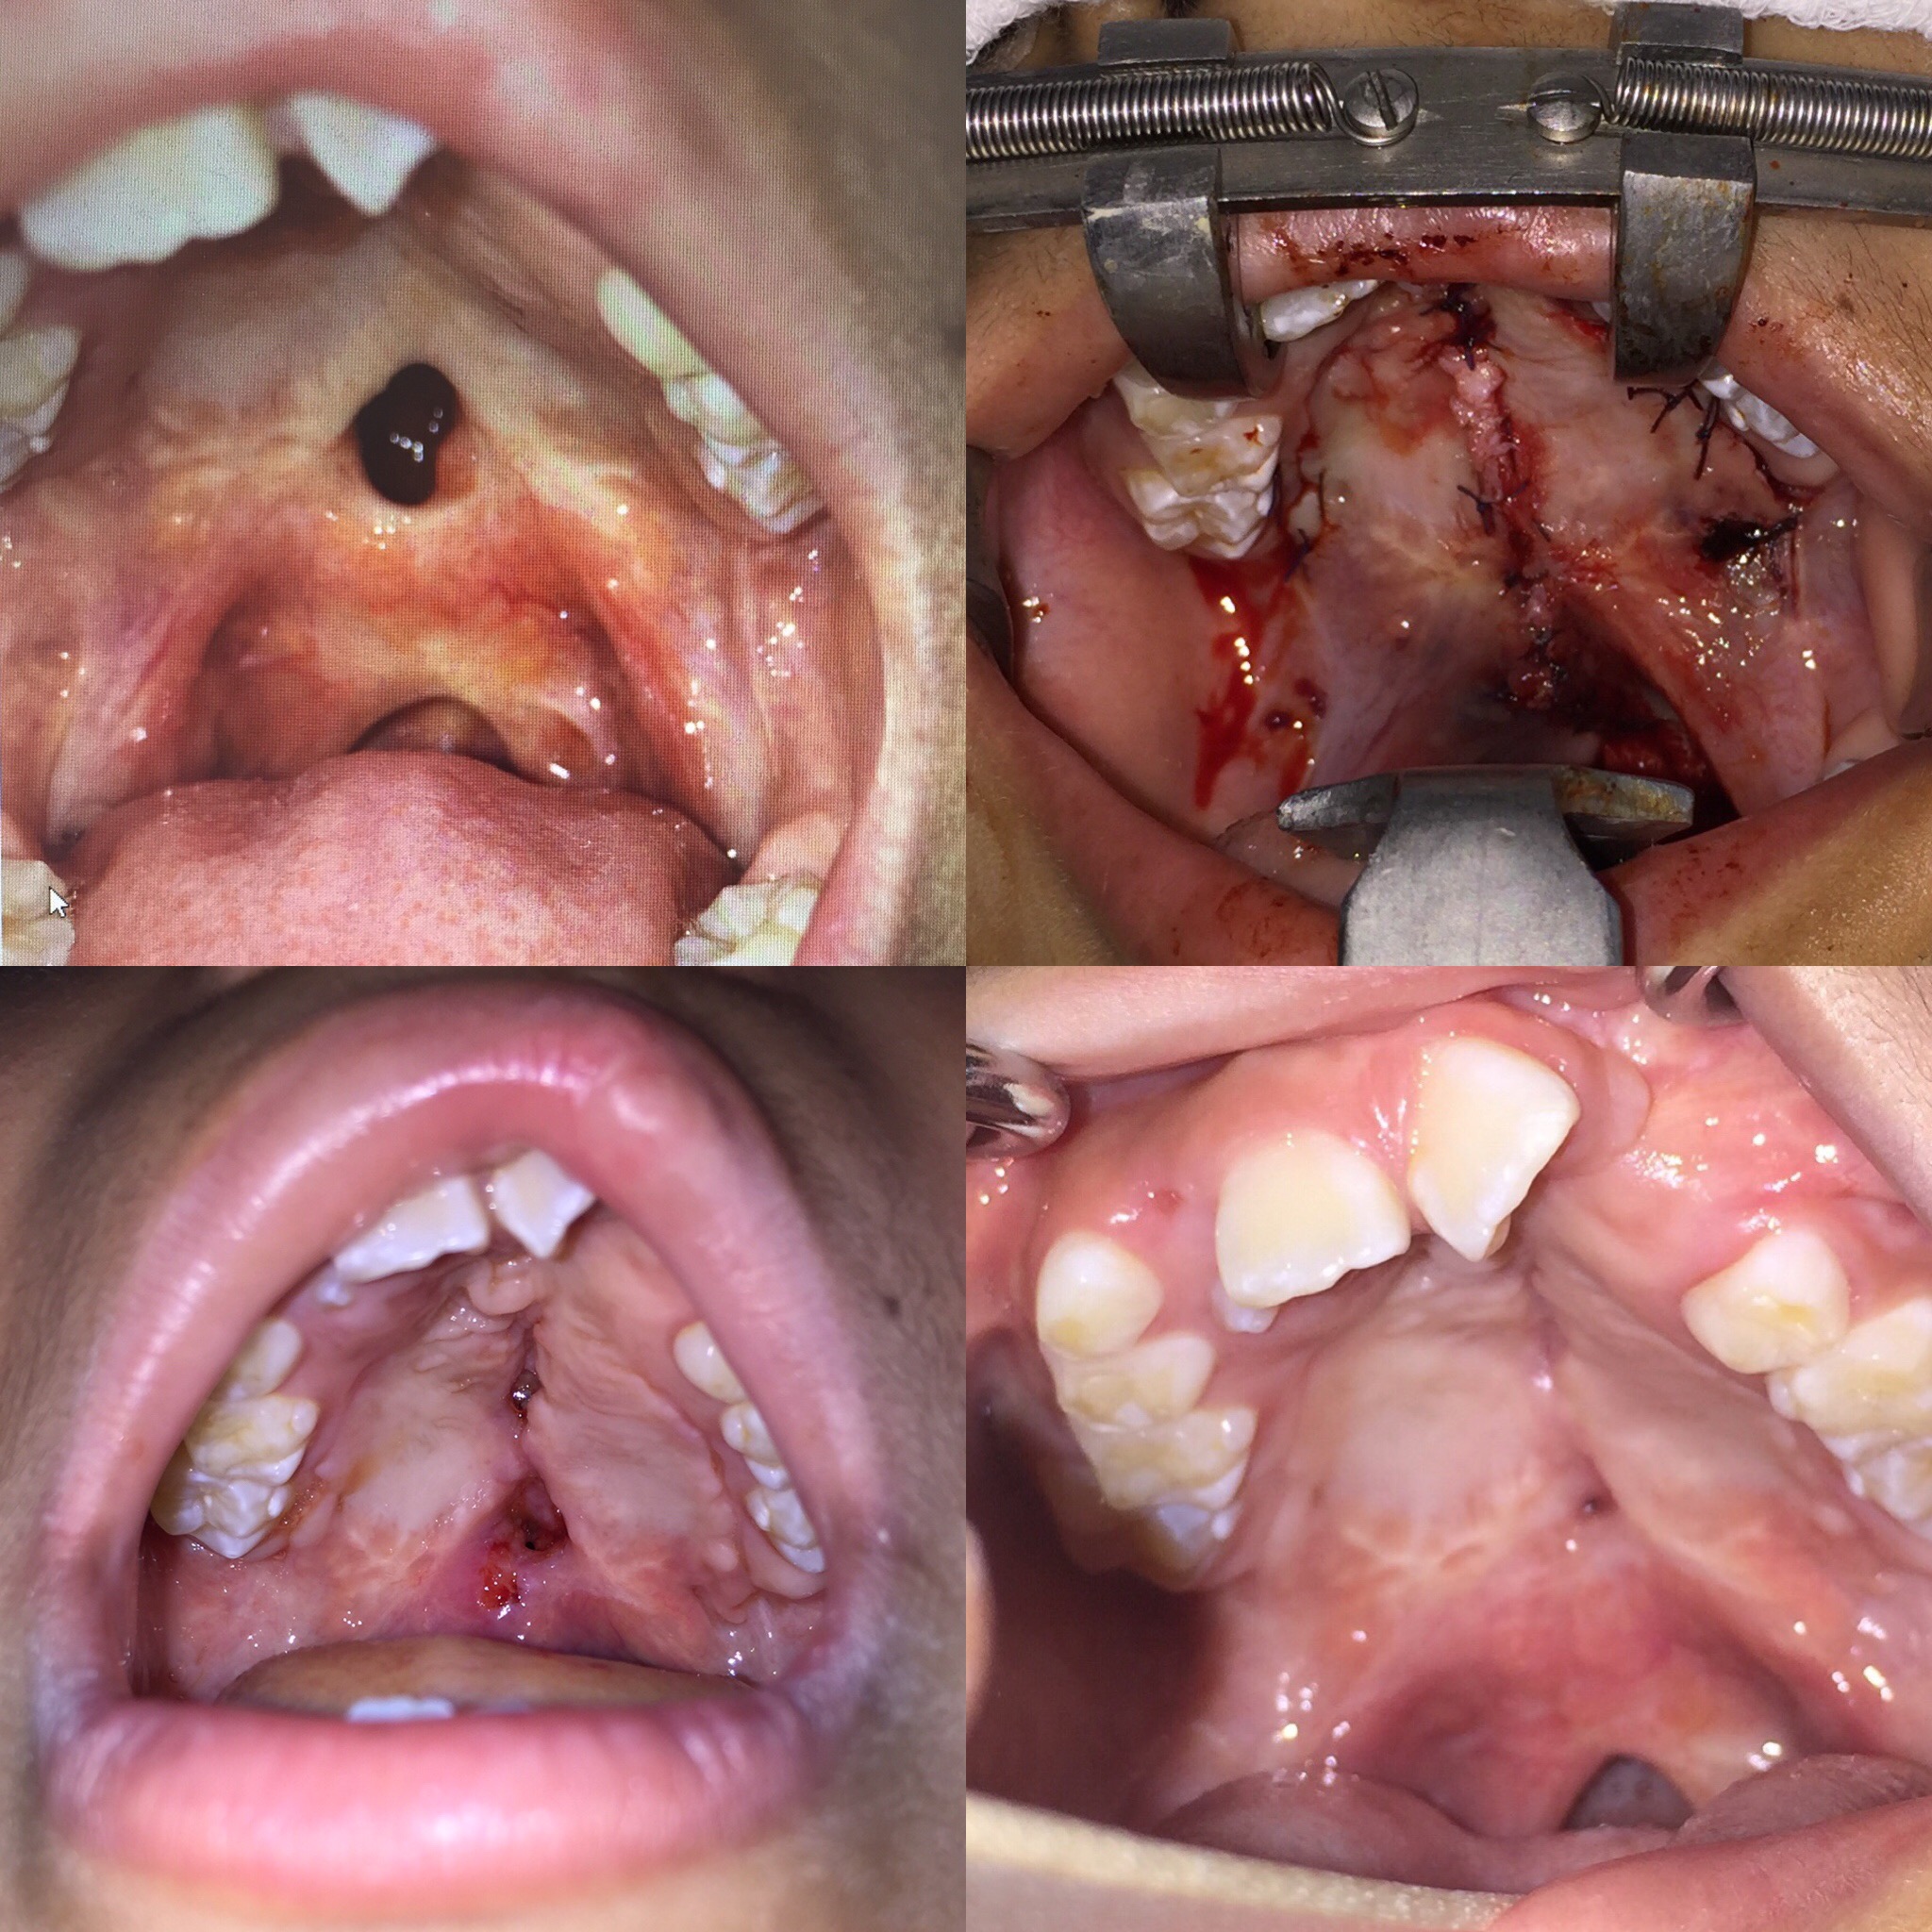

Cirugía de Paladar en pacientes con fisura labiopalatina. Técnica Asensio.

Cirugía de secuela de fisura de paladar, cerrada con Técnica Asensio